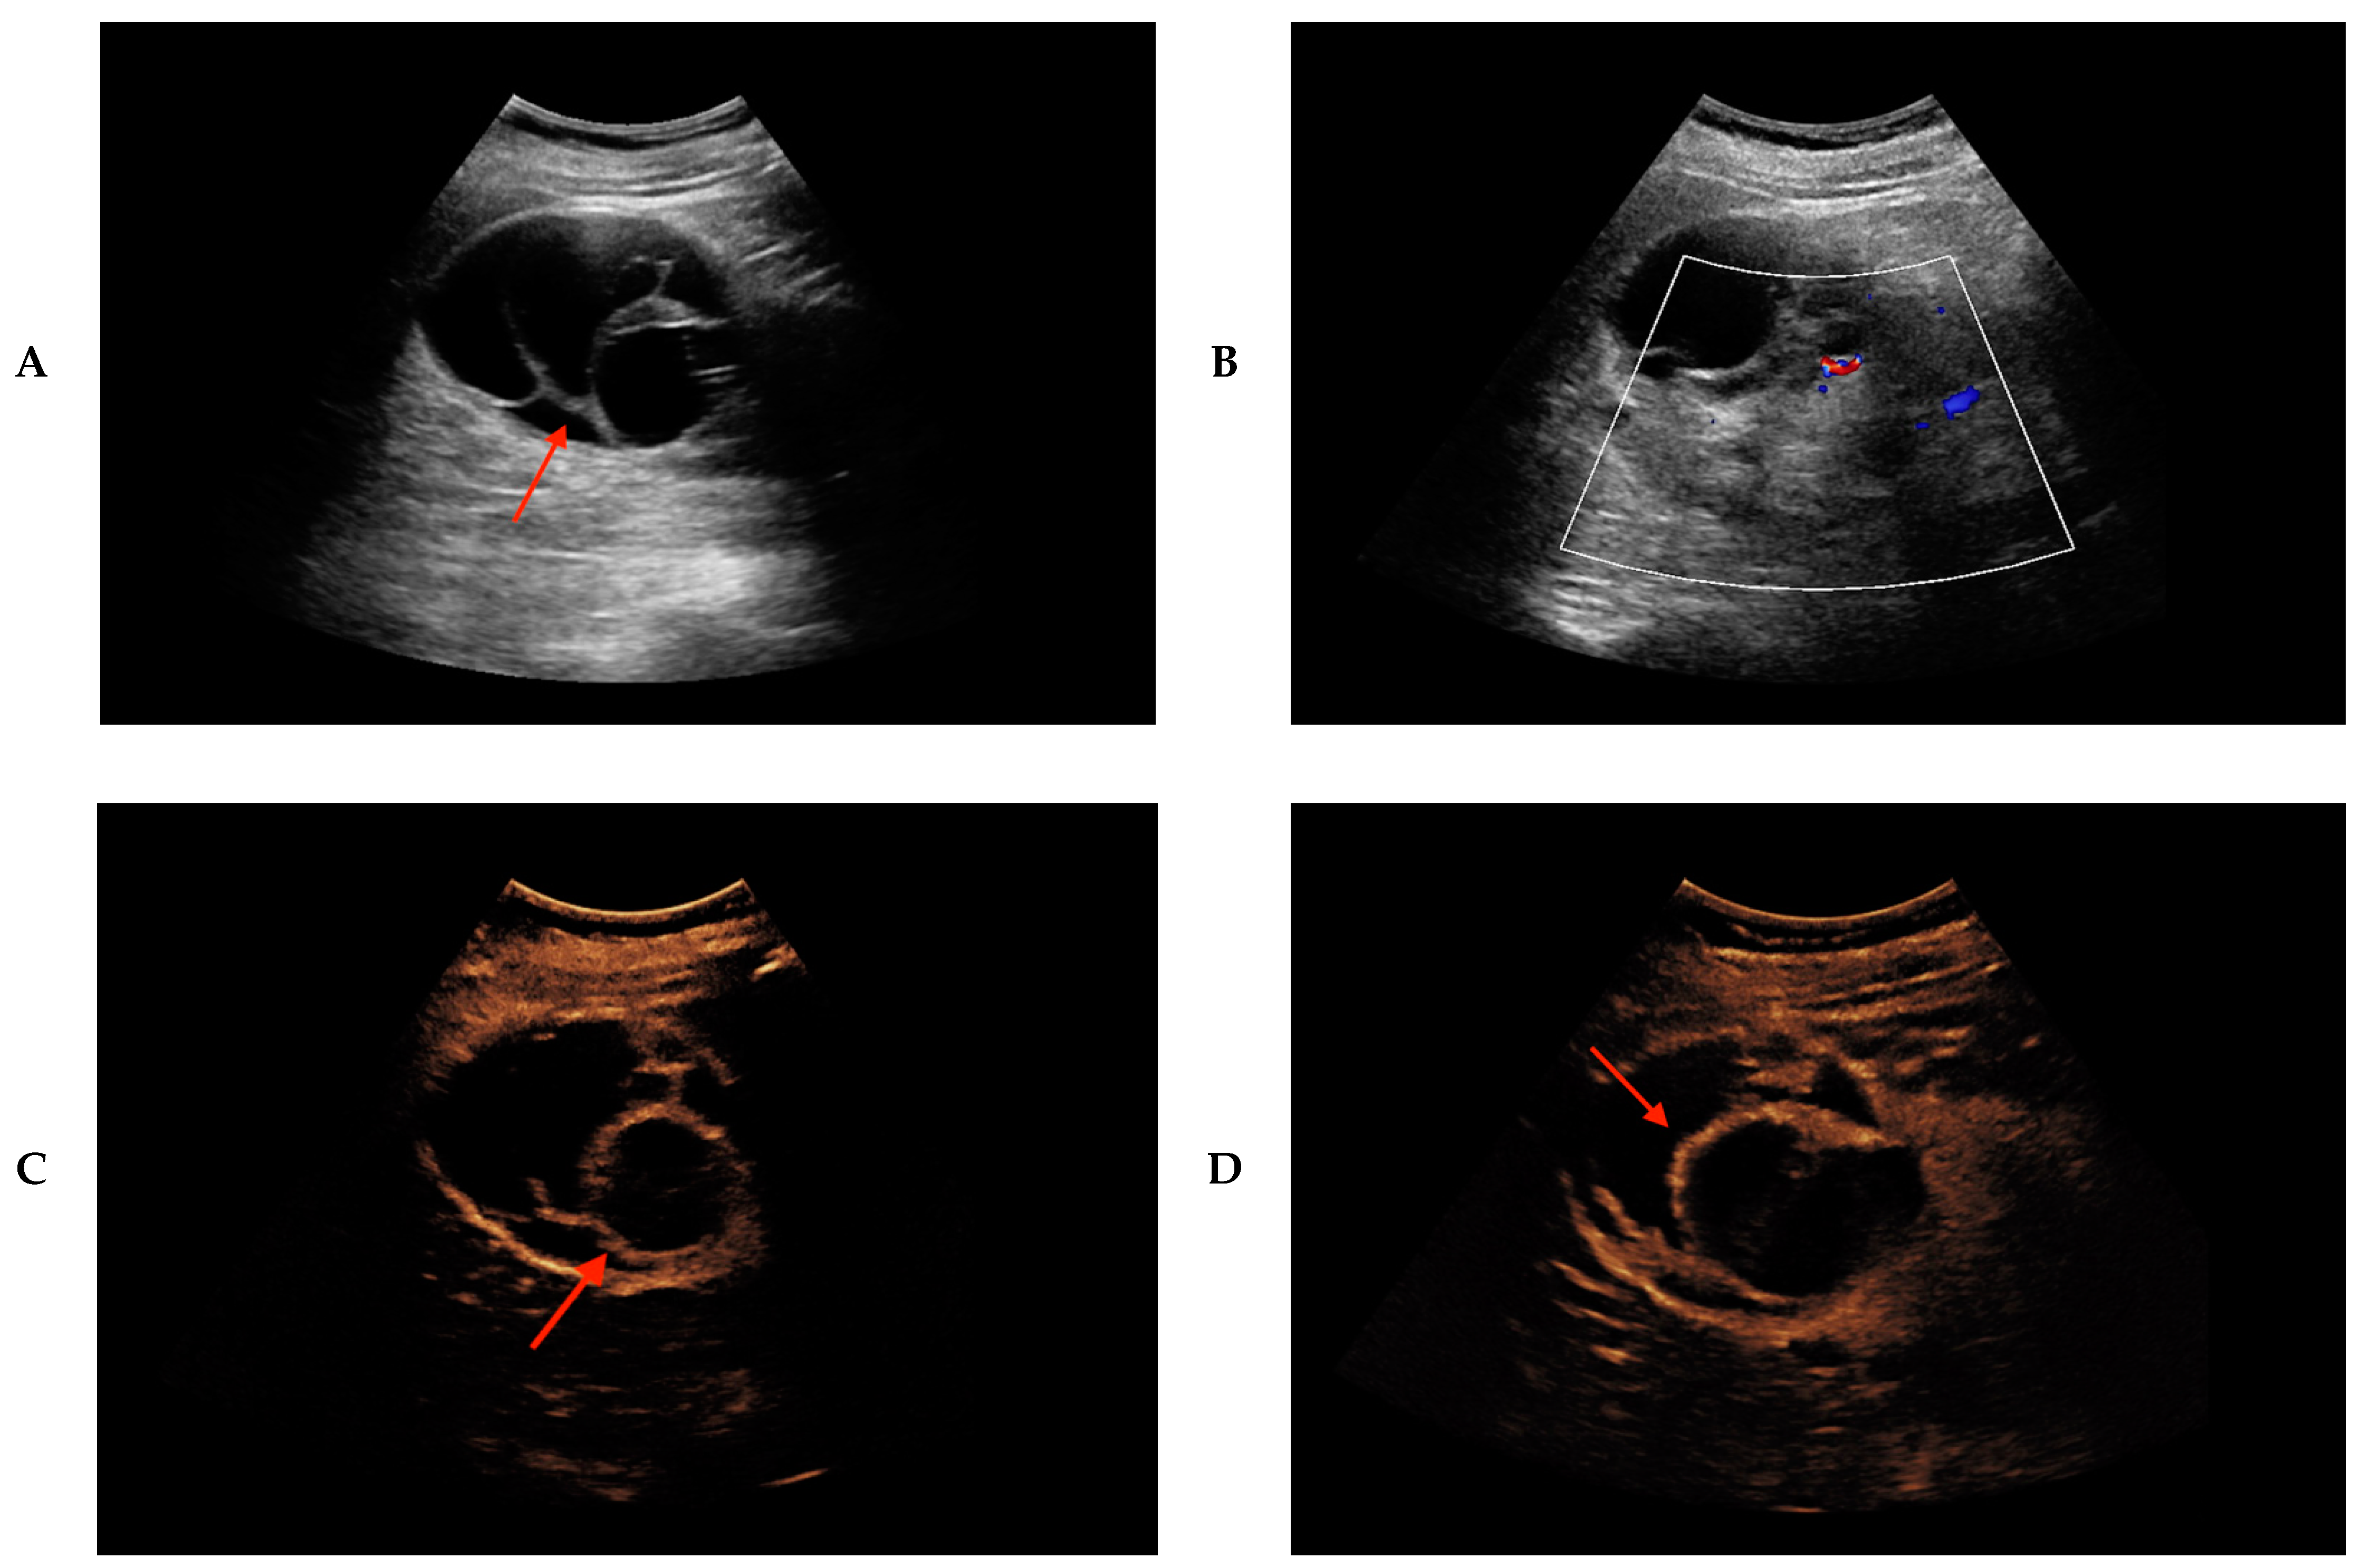

2. Results

4. Materials and Methods

- Mu, J.; Mao, Y.; Li, F.; Xin, X.; Zhang, S. Superb microvascular imaging is a rational choice for accurate Bosniak classification of renal cystic masses. Br. J. Radiol. 2019, 92, 20181038. [Google Scholar] [CrossRef] [PubMed]

- Rubenthaler, J.; Bogner, F.; Reiser, M.; Clevert, D.A. Contrast-Enhanced Ultrasound (CEUS) of the Kidneys by Using the Bosniak Classification. Ultraschall Med. 2016, 37, 234–251. [Google Scholar] [CrossRef]

- Park, B.K.; Kim, B.; Kim, S.H.; Ko, K.; Lee, H.M.; Choi, H.Y. Assessment of cystic renal masses based on Bosniak classification: Comparison of CT and contrast-enhanced, U.S. Eur. J. Radiol. 2007, 61, 310–314. [Google Scholar] [CrossRef]

- Siracusano, S.; Bertolotto, M.; Ciciliato, S.; Valentino, M.; Liguori, G.; Visalli, F. The current role of contrast-enhanced ultrasound (CEUS) imaging in the evaluation of renal pathology. World J. Urol. 2011, 29, 633–638. [Google Scholar] [CrossRef] [PubMed]

- Bertolotto, M.; Cicero, C.; Perrone, R.; Degrassi, F.; Cacciato, F.; Cova, M.A. Renal Masses with Equivocal Enhancement at CT: Characterization with Contrast-Enhanced Ultrasound. AJR Am. J. Roentgenol. 2015, 204, W557–W565. [Google Scholar] [CrossRef] [PubMed]